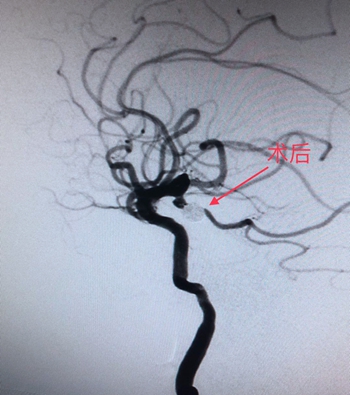

“沙场老将”力挽狂澜

从入院到入手术室,用时不到30分钟。经得患者家属同意,在麻醉科医生精准麻醉和严密检测下,手术由神经外科主任、神经介入科主任廖驭国作主刀,在神经外科李海堃副主任医师的配合下为患者进行颅内动脉瘤栓塞术,术中造影见患者血管迂曲成角,使导丝的通过造成困难和挑战,手术难度极高。廖主任凭借“久经沙场”的经验,以“绣花”功夫,最终完美栓塞破裂动脉瘤,顺利完成手术。

(术前DSA图)                                                        (术后DSA图)